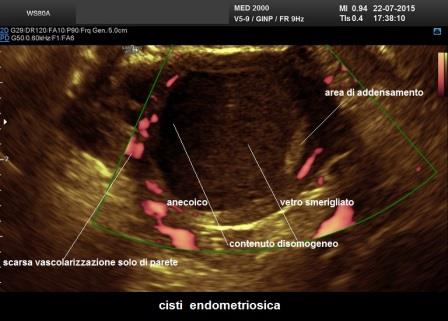

E' la localizzazione più frequente della patologia endometriosica rappresentando circa il 65% dei casi; gli aspetti ecografici più comuni delle cisti endometriosiche ovariche o endometriomi sono:

- cisti uniloculare o multiloculare con un massimo di 4 concamerazioni;

- contenuto "ground glass" ("a vetro smerigliato") legato all'accumulo di cellule ematiche che sfaldano dalla parete e di emosiderina;

- presenza di foci iperecogeni di parete;

- parete esterna della cisti spessa a superficie regolare;

- modesta vascolarizzazione di parete.

In un 35% dei casi gli aspetti degli endometriomi sono meno tipici:

- presenza di sottili setti intracistici che danno origine a cisti multiloculari;

- contenuto disomogeneo per la presenza di aree a differente ecogenicità, iperecogene o ipoecogene, legate ad un addensamento del contenuto cistico (sludge) o a coaguli;

- presenza di irregolarità di parete.

In questi casi sono di aiuto per una corretta diagnosi:

- il power doppler che consente di valutare la presenza di scarsa vascolarizzazione di parete e la assente vascolarizzazione delle aree di addensamento e delle irregolarità di parete;

- esercitando una lieve pressione con la sonda TV è possibile ricercare i movimenti delle strutture endocistiche (sludge e coaguli).